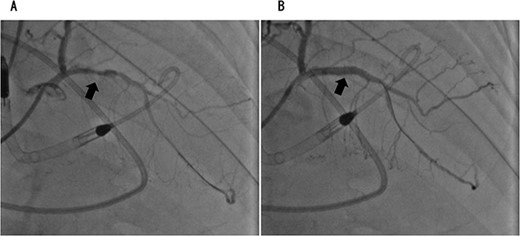

Coronary angiography showed 90% occlusion of the left anterior descending branch (A). After the procedure, the occlusion was completely released (B).